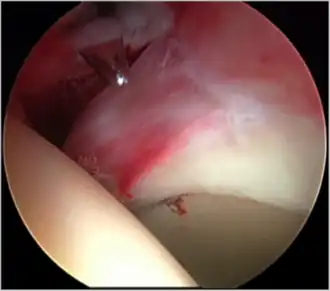

Figure 5. Portal placement under direct vision. The instrument is entering the joint through the hip capsule, between the femoral head (on the left) and acetabular labrum (on the right)

Standard arthroscopic treatment of symptomatic cam FAI involves debridement (resection) or repair of any labral [10] and chondral injuries [11] in the central compartment of the hip, and subsequent reshaping of the head-neck junction of the upper femur (osteochondroplasty) in the peripheral compartment [12][13] using high-speed motorised burrs that are similar in design to a dentist's drill (see fig. 9).